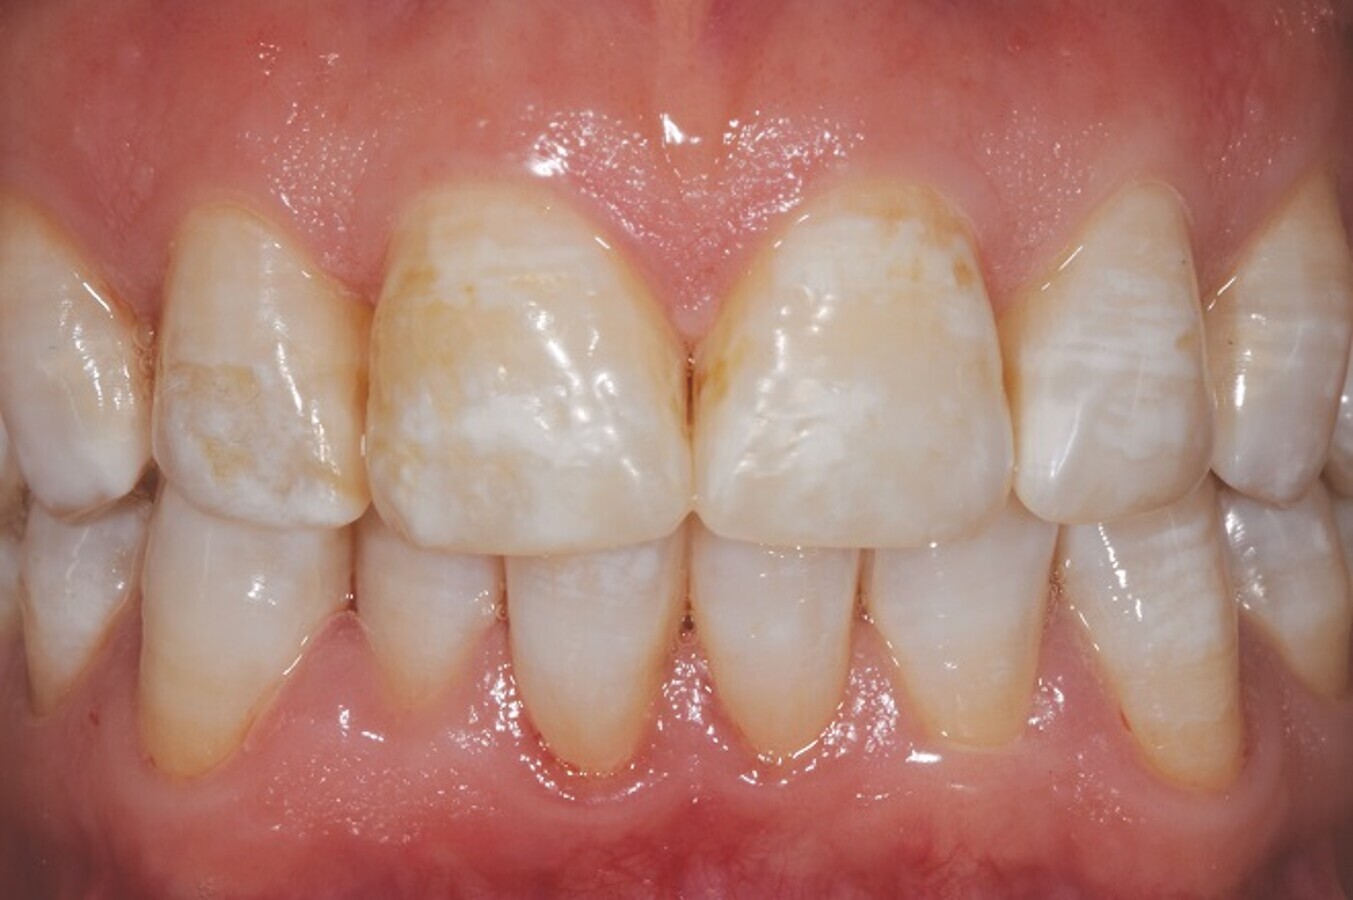

Slika 3: Po 70 dneh.

Pacientka je izkazala visoko stopnjo sodelovanja pri zdravljenju in po predpisanem protokolu, opazila je tudi klinične izboljšave, pa ne le po videzu (fotografiji na slikah 2 in 3 sta posneti po 30 in 70 dneh), temveč tudi glede občutka, tako da je poročala o zmanjšani občutljivosti zob. Pri pregledih lahko opazimo izboljšanje indeksa zobnih oblog ter zmanjšano poroznost zaradi izboljšanja teksture sklenine in dentina.